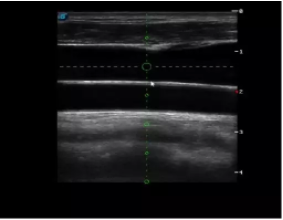

實(shí)時(shí)觀察穿刺針進(jìn)入血管的全過程,方便操作及較短的穿刺路徑,智能進(jìn)針尺寸提示,讓置管工作更加輕松,高效。

不同進(jìn)針路徑